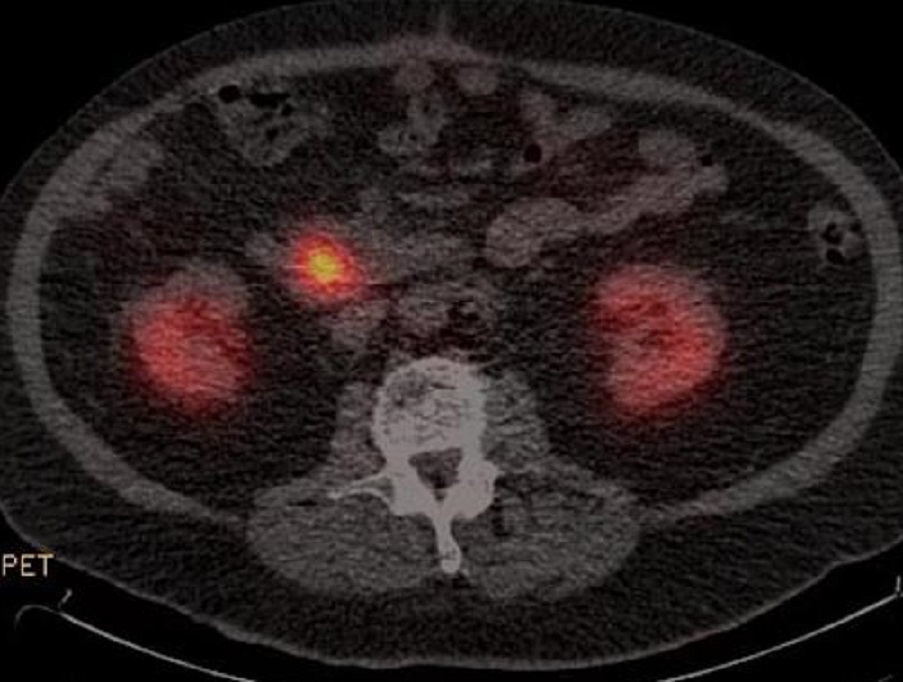

Scintigraphie et

PET - CT : Technique de choix pour

rechercher , differentier les tumeurs primitives et en

realiser le bilan de l'extention locaux regional ou a

distance . Sa sensibilite

se dépendre du siège de la tumeur primitive, du type de

secrétions et de la taille de la tumeur , ce qui est bien

sur les gastrinomes a taille de plus 2cm et elle est limite

pour la detection des tumeurs primitives et des metastases a

taille moidre de 1,5cm . Le PET-CT est mal limite pour

diagnostic differetielle

Aspect radiologique PET -CT d'une tumeur

endocrine de latete du pancreas . N'a pas de foyer

de l'extention metastatique se retrouver |